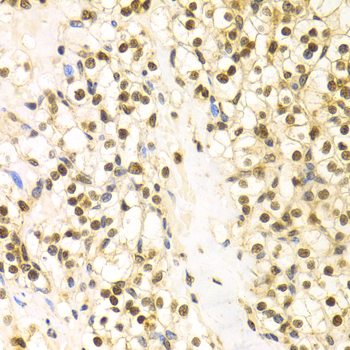

Immunohistochemistry of paraffin-embedded human kidney cancer using BAG1 antibody at dilution of 1:100 (x400 lens).

Immunohistochemistry of paraffin-embedded human kidney injury using BAG1 antibody at dilution of 1:100 (x400 lens).

Immunohistochemistry of paraffin-embedded human esophageal cancer using BAG1 antibody at dilution of 1:100 (x400 lens).